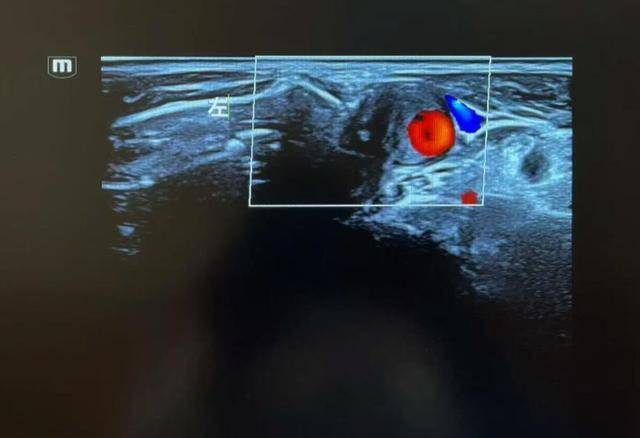

直到有一天,他在早市突然眼前一黑,差点摔倒。家人连忙送去医院,一查彩超,医生皱起了眉:“你的颈动脉堵了差不多70%,再拖下去,很容易发展成脑中风。”

判断颈动脉堵塞严重不严重,医生一般会两头一起看影像学检查结果:例如颈动脉彩超、CTA,直接看到血管腔狭窄的比例症状:有没有上述反复头晕、记忆力变差、小中风等表现。